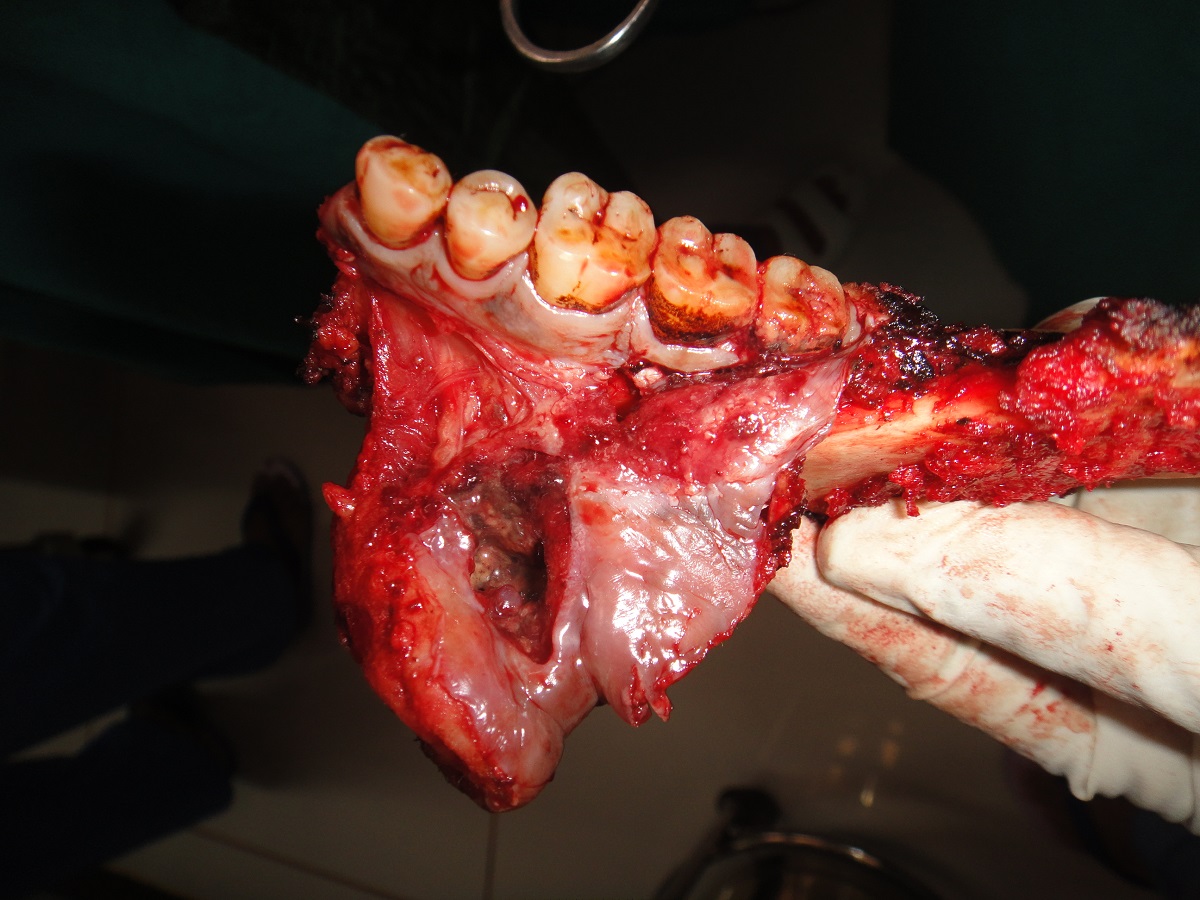

75 yrs old patient having right upper alveolus carcinoma.patient was operated for right buccal mucosa carcinoma in 2009.pet ct shows localised disease with minimal uptake in left neck node.Right subtotal maxillectomy done with Right PM flape.